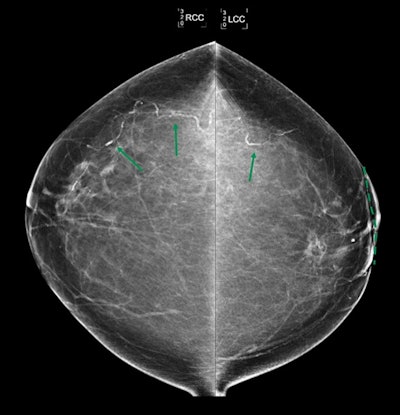

Bilateral craniocaudal views show bilateral breast arterial calcification in a 71-year-old patient with history of left breast invasive lobular carcinoma treated with wide local excision and radiation therapy with 50.4 Gy and 10 Gy boost to tumor bed (scar market indicated dashed line). Mammogram obtained 4 years after completion of radiation therapy. Breast arterial calcification is more extensive in untreated right breast than in left breast that received radiation therapy. Image and caption courtesy of the ARRS.Bilateral craniocaudal views show bilateral breast arterial calcification in a 71-year-old patient with history of left breast invasive lobular carcinoma treated with wide local excision and radiation therapy with 50.4 Gy and 10 Gy boost to tumor bed (scar market indicated dashed line). Mammogram obtained 4 years after completion of radiation therapy. Breast arterial calcification is more extensive in untreated right breast than in left breast that received radiation therapy. Image and caption courtesy of the ARRS.